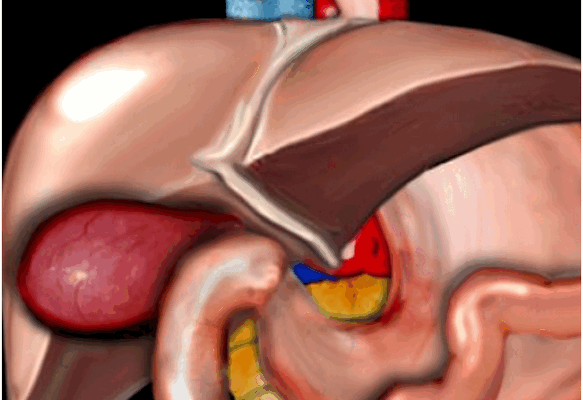

Образование желчи в печени - процесс непрерывный, однако поступление ее в кишечник в норме происходит преимущественно в процессе пищеварения. Это обеспечивается резервуарной функцией желчного пузыря и его ритмическими сокращениями с последовательным расслаблением сфинктера Люткенса и далее сфинктера Одди, расположенного в месте впадения общего желчного протока в кишку (рис. 1).

1 - дно желчного пузыря;

2 - пузырный проток;

3 - собственная печеночная артерия;

4 - воротная вена;

5 - желудочно-печеночная связка;

6 - левая доля печени;

7 - хвостатая доля печени;

8 - нижняя полая вена;

9 - хвостатый отросток;

10 - шейка желчного пузыря;

11 - правая доля печени;

12 - тело желчного пузыря;

13 - квадратная доля печени.